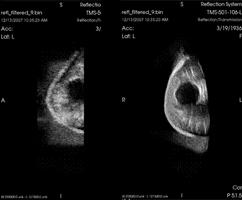

January 19, 2011 – TechniScan, a medical device company engaged in the development and commercialization of an automated 3-D breast ultrasound imaging system, said this week it signed a product development agreement with Womens3D Inc. In the deal, worth a minimum of $1.5 million, TechniScan and Womens3D will co-develop technology specifically for Womens3D's proposed target market that is directed toward women's health practices. Under the terms of the agreement, Womens3D acquired a prototype of the TechniScan WBU system for $250,000 and contemplates contributing at least $1.25 million more to support development of a specialized whole breast ultrasound imaging system based on the TechniScan Warm Bath Ultrasound (WBU) product now in clinical testing. In addition, TechniScan will supply technical support of the product and customization of the imaging network applications that will be used in part to store and transmit the image files. "As a part of the development agreement, we purchased a prototype WBU system for evaluation, and we are now very excited to be working with TechniScan and welcome their expertise as we address the needs of the developing markets in women's health," said Scott Sanders, Womens3D CEO. Womens3D's Chief Science Officer Mark Lenox, Ph.D., formerly part of the engineering team that performed the research and early development and commercialization of positron emission tomography (PET) in nuclear medical imaging, conducted the technical evaluation of TechniScan's WBU system. TechniScan's Warm Bath Ultrasound (WBU) system is designed to capture three-dimensional images of the breast as a woman lies prone on a table while proprietary ultrasound technology in a warm water tank images the breast anatomy. This new method of imaging produces diagnostic information that is not available with traditional hand-held ultrasound or whole breast ultrasound systems presently on the market. "TechniScan is excited to be working with Womens3D on this development program, which potentially will open new markets for our equipment and add a valuable partner to our development efforts. Over the next one to two years we expect to complete the development of an ultrasound system for Womens3D based on our technology," said Dave Robinson, TechniScan CEO. TechniScan's WBU imaging device is limited by U.S. law to investigational use. For more information: www.tsni.com, www.Womens3D.com